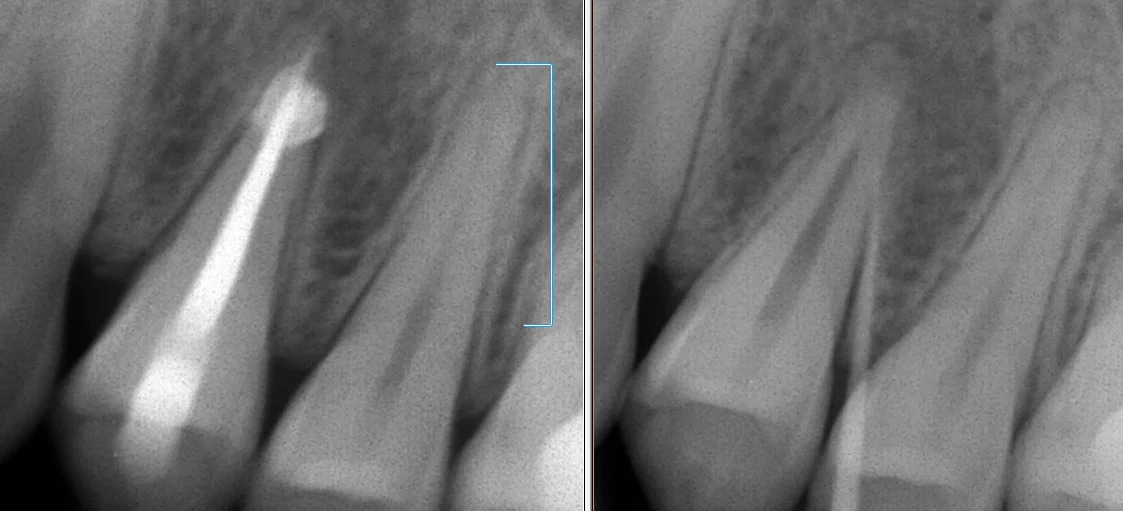

今回は神経の治療が終わった時のレントゲンからです。

右が術前に膿の袋にレントゲンに写る柔らかい棒状のものを刺してレントゲンを撮ったもの。

左が最終的なお薬を詰め終わったところです。

口の中にある、ニキビのようなところにこういう材料を入れて撮影することで、その膿がどの歯・どの根から出てるのかを判断できるので、非常に便利です。

デメリットは変なところに刺さると痛いことですね・・・(;'∀')

今回の場合だと、根っこが2本ありますが、そのうちの1つの方がニキビの原因になっている状態でしたね。